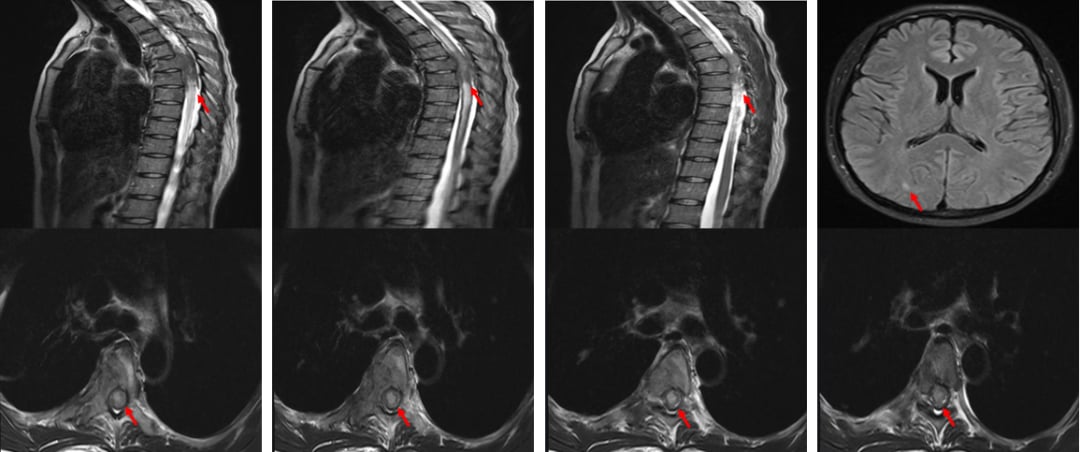

在五线治疗失败后,患者的病情急转直下。2024年3月,她出现了右下肢沉重感,并迅速发展为腹部以下感觉丧失、双下肢0级肌力(完全瘫痪)和大小便失禁。影像学检查证实,癌细胞已侵犯至脊髓,同时伴有脑转移,生命危在旦夕。

影像科专家详细解读了MRI表现,认为病变来源于髓外硬膜下,压迫脊髓。肿瘤科专家则认为,全身治疗(如T-DXd)联合局部放疗是处理此类危重情况的有效策略。本病例的成功,也验证了这一组合的威力。